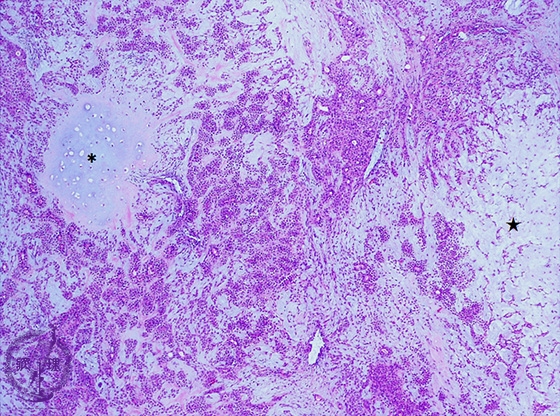

Microscopic finding (HE stain, low-power view):Pleomorphic adenoma shows divergent morphological features. There are tubular and trabecular structures composed of epithelial cells with an intermingled myxomatous (★) and chondroid stroma (*).